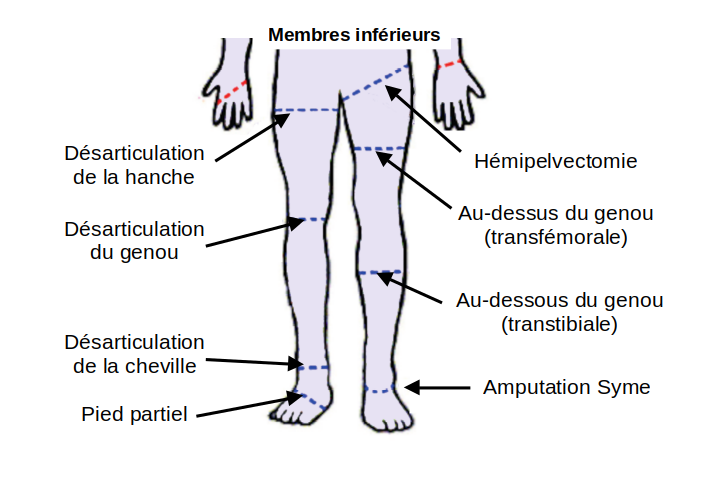

Les amputations du

membre inférieur

Amputation à plusieurs niveaux

Hémipelvectomie

Désarticulation de hanche

Amputation transfémorale (au-dessus du genou)

Désarticulation du genou

Amputation transtibiale (en dessous du genou)

Amputation du pied

Amputation de Syme